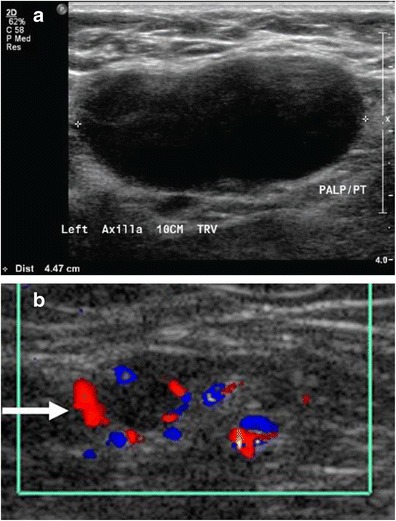

의료 초음파에서 B-모드 영상은 림프절 형태를 보여주며, 파워 도플러는 혈관 패턴을 평가할 수 있다.[28] 전이와 림프종을 구별할 수 있는 B-모드 영상 특징에는 크기, 모양, 석회화, 힐룸 구조의 소실, 림프절 내 괴사가 포함된다.[28] 연조직 부종과 B-모드 영상에서 림프절 유착은 결핵성 경부 림프절염 또는 이전 방사선 치료를 시사한다.[28] 림프절 크기와 혈관의 일련의 모니터링은 치료 반응을 평가하는 데 유용하다.[28]

의료 초음파에서 B-모드 영상은 림프절 형태를 보여주며, 파워 도플러는 혈관 패턴을 평가할 수 있다.[28] 전이와 림프종을 구별할 수 있는 B-모드 영상 특징에는 크기, 모양, 석회화, 힐룸 구조의 소실, 림프절 내 괴사가 포함된다.[28] 연조직 부종과 B-모드 영상에서 림프절 유착은 결핵성 경부 림프절염 또는 이전 방사선 치료를 시사한다.[28] 림프절 크기와 혈관을 일련으로 모니터링하는 것은 치료 반응을 평가하는 데 유용하다.[28]

액와 림프절의 림프절병증은 지방 융기가 없는 15mm 이상인 고형 림프절로 정의될 수 있다.[36] 액와 림프절은 지방으로 구성된 경우 최대 30mm까지 정상일 수 있다.[36]